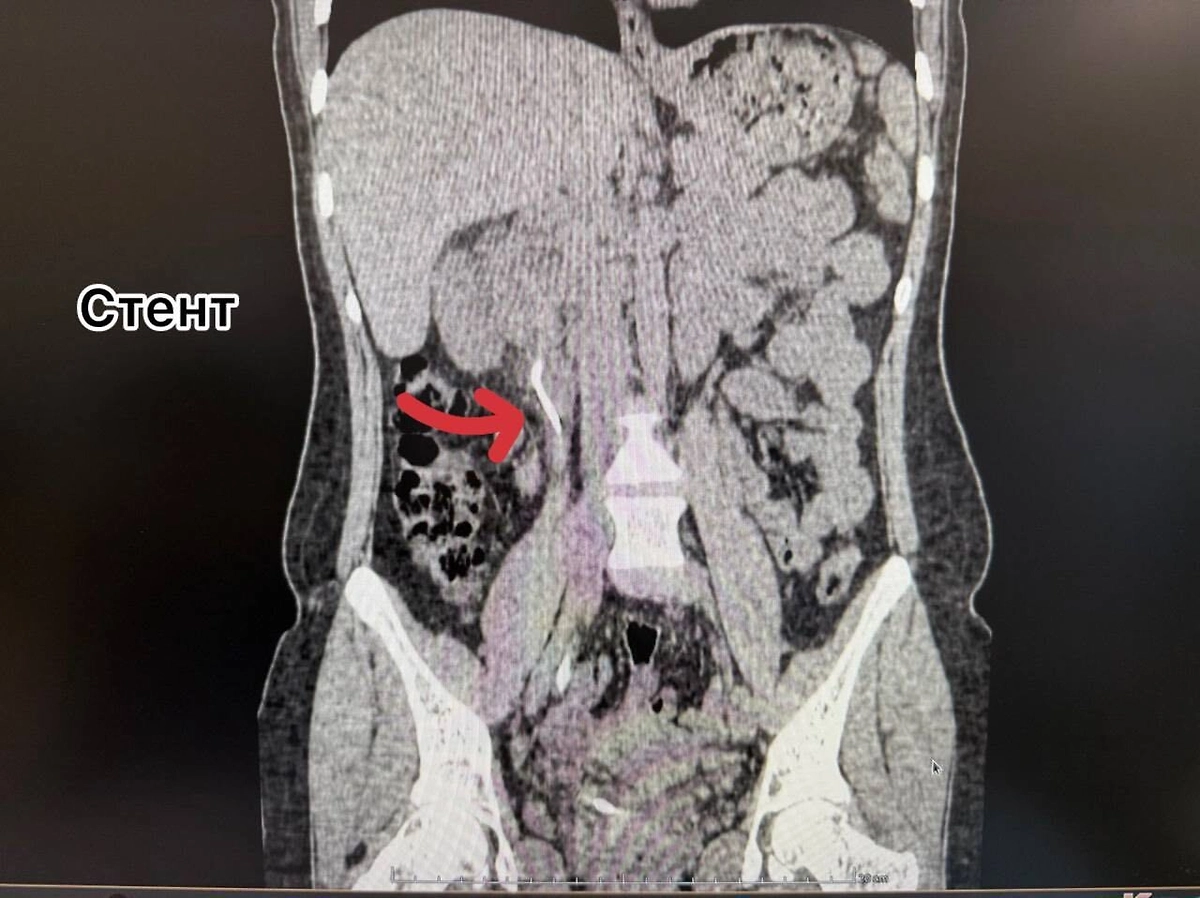

Как оказалось, два года назад женщине установили мочеточниковый стент, но вовремя его не удалили, из-за чего инородный предмет превратился в плотную структуры, а в почке и мочевом пузыре образовались камни. Врачи за раз провели многоэтапную операцию — удалили и стент, и образования в органах.

«Через один минимальный прокол в пояснице (метод перкутанной нефролитотрипсии) с помощью ультразвука был разрушен и удалён почечный камень. Одновременно, через естественные пути, современным лазером Urolase+ Premium был раздроблен и извлечен камень из мочевого пузыря и стент. Операция проводилась с применением эндоскопического оборудования и под рентген-контролем, что гарантировало высочайшую точность», — говорится в сообщении.

Рентген женщины с вросшим стентом во Владивостоке. Обложка © Telegram / Тысячекоечная больница г. Владивосток